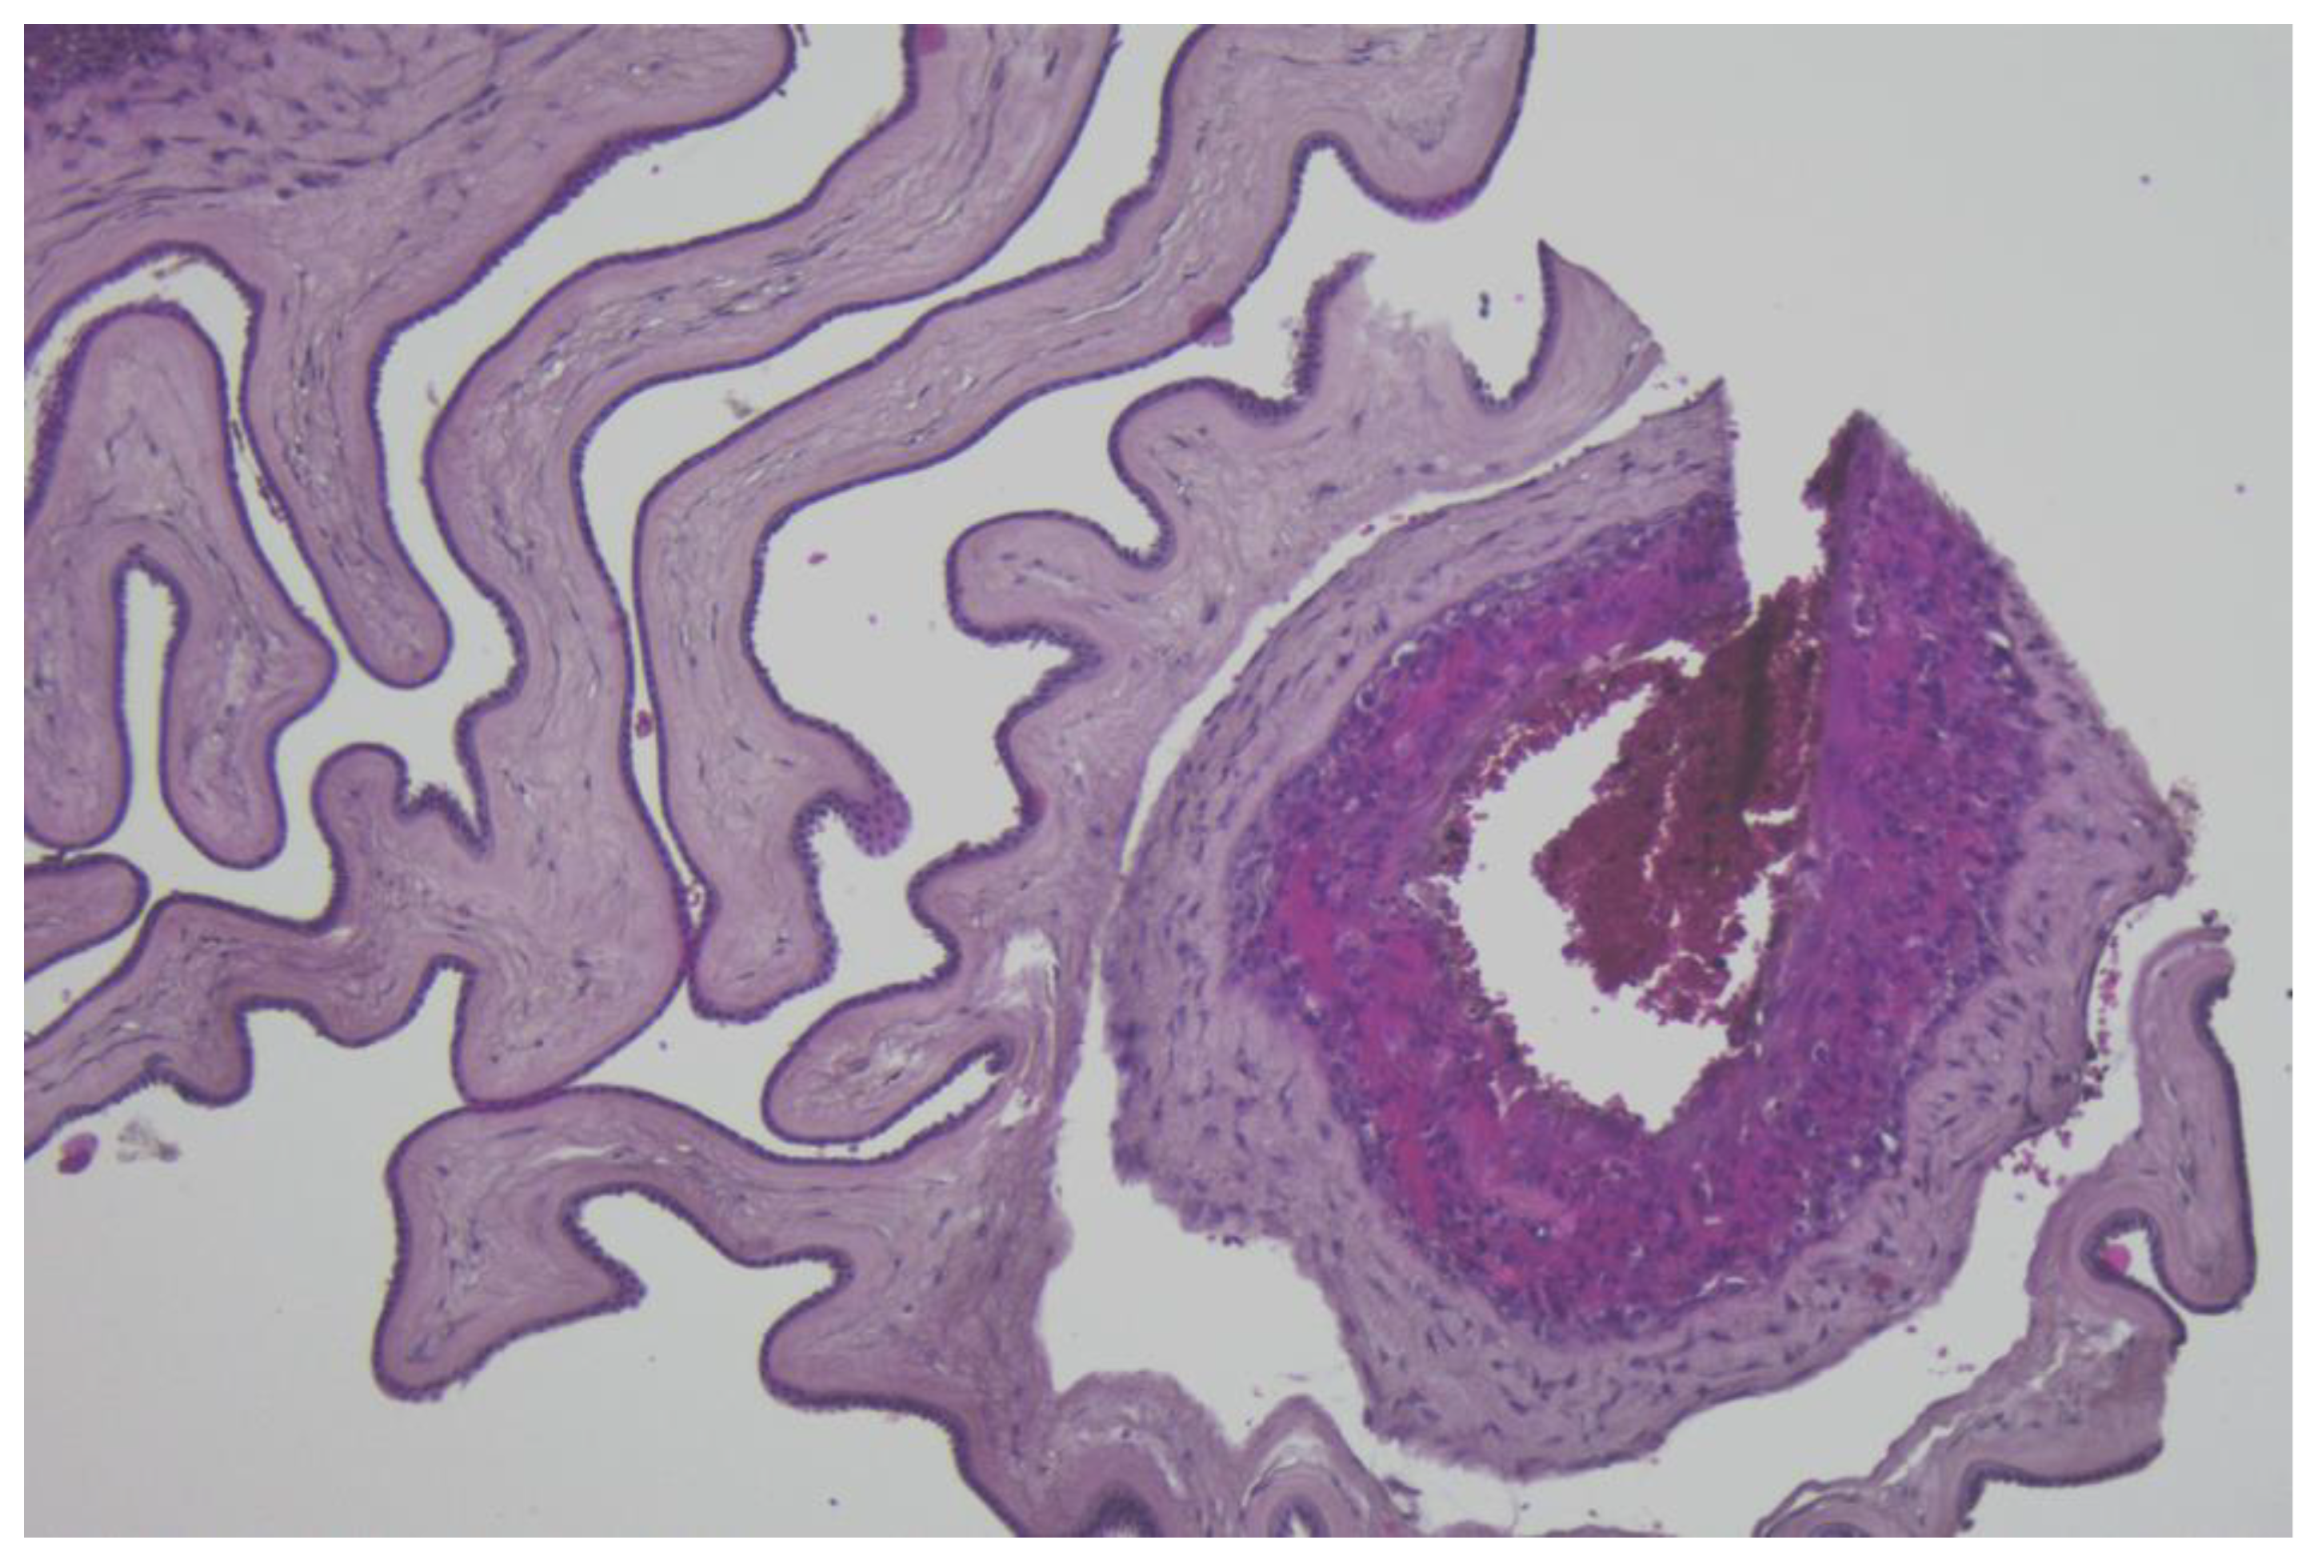

- Resta, L.; Vimercati, A.; Cazzato, G.; Fanelli, M.; Scarcella, S.V.; Ingravallo, G.; Colagrande, A.; Sablone, S.; Stolfa, M.; Arezzo, F.; et al. SARS-CoV-2, Placental Histopathology, Gravity of Infection and Immunopathology: Is There an Association? Viruses 2022, 14, 1330. [Google Scholar] [CrossRef] [PubMed]